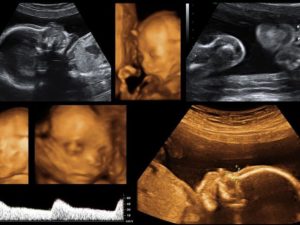

Третье Узи При Беременности На Каком Сроке

Третье УЗИ при беременности — на каком сроке его сделают, решает врач. В норме выполняется в третьем триместре после 30 недели, но в тех ситуациях, когда женщине требуются дополнительные обследования, ультразвуковые исследования проводят чаще, третье проводится на более ранних сроках.

Многих девушек интересует, третье УЗИ при беременностях на каком сроке выполняется? Основная задача исследования ультразвуком – определение того, в насколько правильном порядке идет развитие ребенка, насколько показатели эмбриона соотносятся со сроком беременности. Показано исследование не только в 3 триместре беременности. Первый и второй никакого исключения не представляют. Плановое УЗИ при беременности выполняется три раза, если отсутствуют показания к дополнительной проверке.

Третье УЗИ при беременности выполняется в период с 30 по 34 неделю.

Период вынашивания ребенка очень ответственный, требующий тщательного контроля со стороны будущей мамы и врача. Если малыш развивается нормально, то УЗИ женщине выполняется три раза. Во время третьего УЗИ при беременности оцениваются важные параметры, в том числе определяющие тактику ведения родов.

Последнее УЗИ, которая женщина проходит при беременности перед родами, является третьим по счету и имеет большое значение. Его проведение в 3 триместре показано всем будущим мамам. С помощью УЗИ специалисты смотрят в 32 недели гестации следующее:

1. Параметры ребенка, рост, вес.

2. Строение внутренних органов на предмет аномалий, недоразвития.

3. Развитие головного мозга.

4. Расположение малыша в матке. Это помогает определить тактику ведения беременности и родов.

5. Пол ребенка.

6. Состояние околоплодных вод, их количество.

7. Степень зрелости плаценты.

8. Кровоток в сосудах пуповины.

9. Состояние родовых путей, готовность к родам, угрозу прерывания беременности.

10. Дыхательные движения плода, активность, частоту сердечных сокращений.

Сроки, в которые делают 3-е УЗИ по беременности, определяются медицинским стандартом ведения женщины.  Обследование проводится с 30-й по 34-ю неделю. Наиболее часто гинекологи назначают делать третий скрининг с помощью УЗИ в 32 недели гестации.